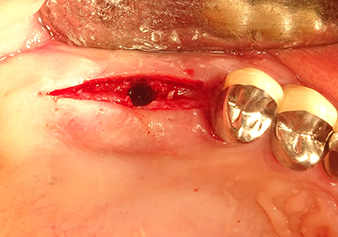

Instruments take over the work

Following atraumatic preparation of the mucoperiosteal flap, the implant position was marked with the I1 instrument and the site prepared – until initial resistance was felt. Piezosurgical instruments were used in an up and down movement without any pressure being exerted. The piezoelectric vibration produced the desired and efficient cavitation.

The I2A instrument (diameter 2.0 mm) was then used to perforate the sinus floor intermittently and on the smallest scale possible. This special piezosurgical method ensures that the Schneiderian membrane is not damaged. When the Z25P was used, the membrane was already lifted slightly by the coolant supplied via the instrument tip (Fig. 3). The coolant quantity was just 50% in order to avoid high pressure in the implant bed.